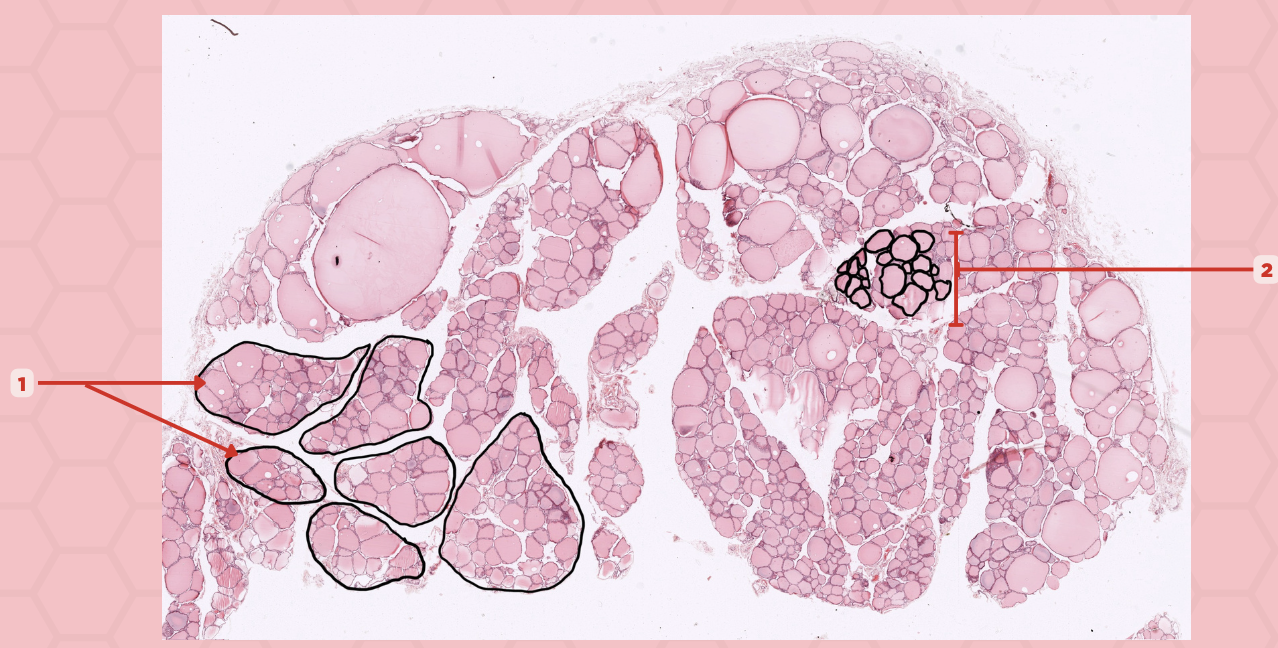

Thyroid

Identify the specimen.

Lobules

Identify the structure labeled as 1.

Follicles

Identify the structure labeled as 2.